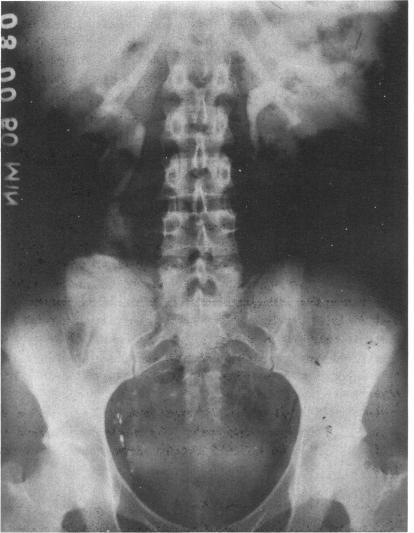

Experience with ileal ureters.

Bull N Y Acad Med. 1977 May;53(4):329-37.

PMID:266412

原文链接:https://pmc.ncbi.nlm.nih.gov/articles/PMC1807295/